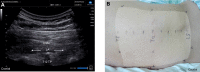

Figures